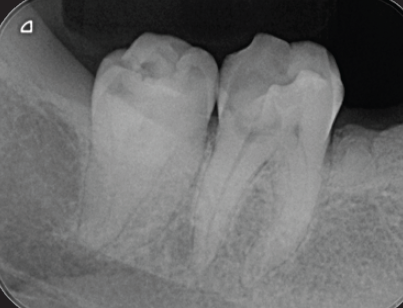

右下6番カリエスが進行し、遠心根根尖部周囲に透過像を認める(図9)。歯髄生活反応(―)

解剖学的形態は複雑な形態で湾曲度も強い。根管口付近の規制を除去してグライドパスを行い、根尖部に適度の抵抗形態を与えるためテーパー形成をニッケルチタンファイルを用いて根管拡大・形成を行った。MTAシーラーを併用しガッタパーチャを用いて根管充填を行った(図10)。

(図9)右下6番はカリエスが進行し、歯髄壊疽から遠心根根尖部に透過像を認める

歯髄腔は狭窄し近心根は複雑な湾曲を呈する

(図10)根管口付近の歯質を処理し、器具が歯軸に対して出来るだけ平行に挿入できるように

修正形成し根管処置を完了した

湾曲根管においてもトランスポーテーションすることなく、

本来の根管の形態を極力維持することができた